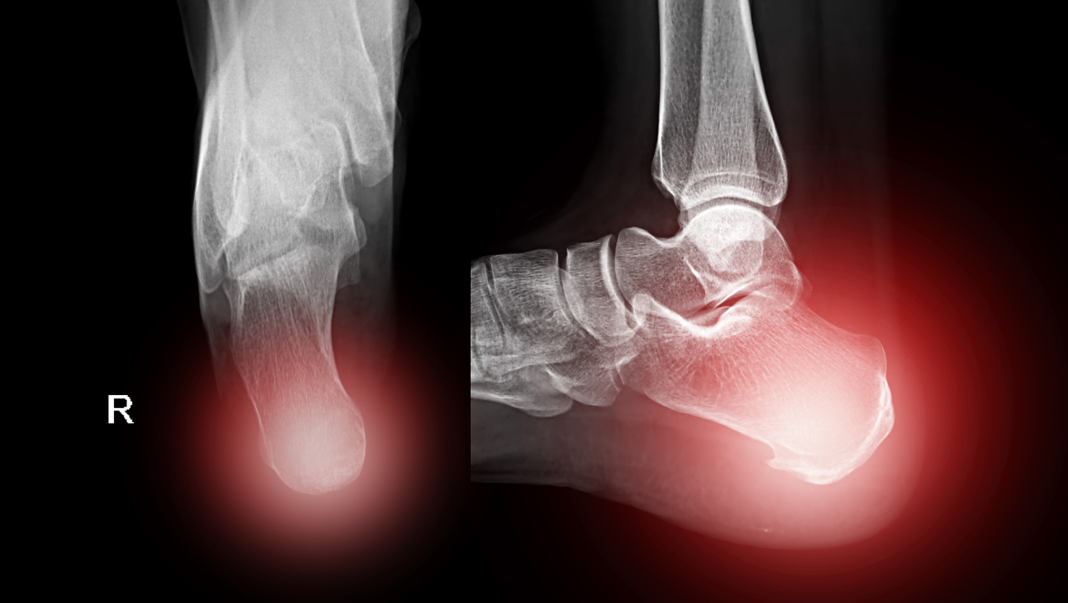

• X-quang gót chân: Phương pháp chẩn đoán hình ảnh tiêu chuẩn, cho thấy rõ ràng hình ảnh gai xương ở mặt dưới xương gót. Đây là bằng chứng xác định sự hiện diện của gai gót chân.

• Siêu âm hoặc MRI: Được sử dụng để đánh giá tình trạng viêm và độ dày của cân gan chân, đặc biệt khi X-quang không đủ thông tin hoặc cần loại trừ các chẩn đoán khác (như nứt gãy xương gót).